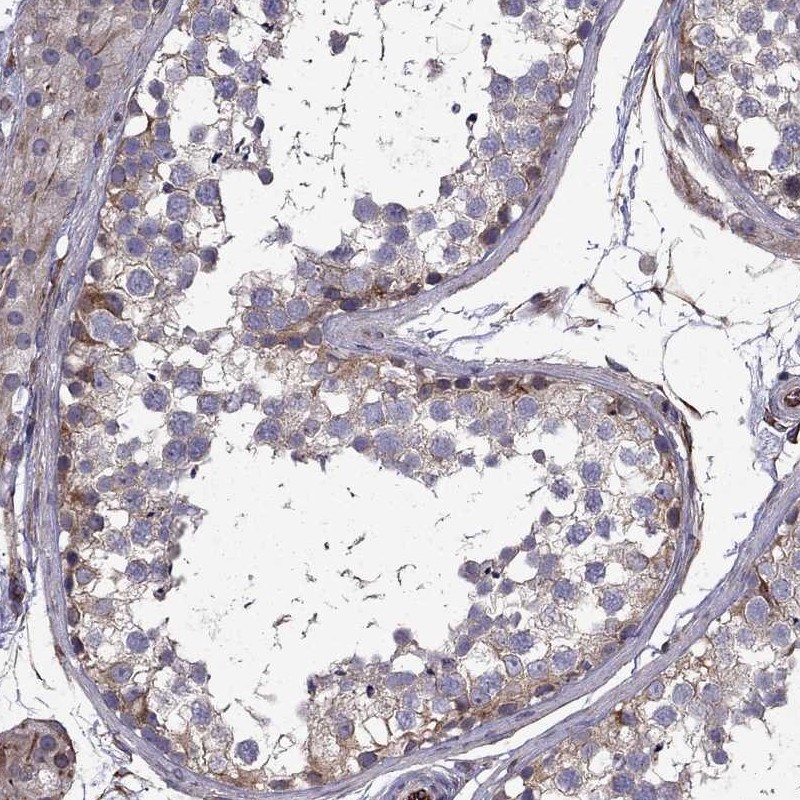

Immunohistochemical staining of human testis shows moderate cytoplasmic positivity in cells in seminiferous ducts.